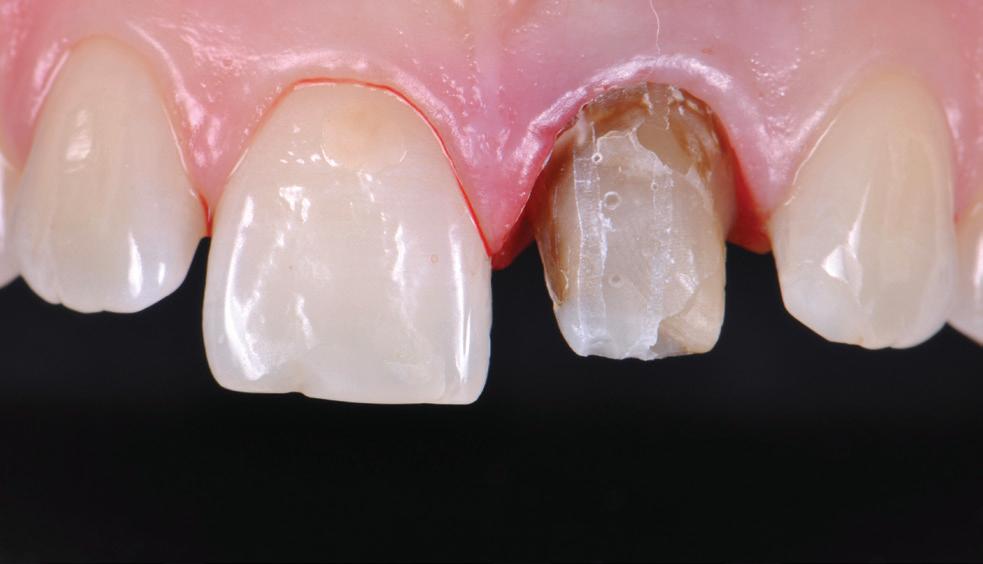

Knowing your own practice.